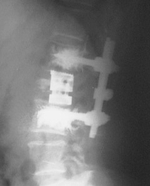

Такой уникальный комплекс хирургически-диагностического оборудования позволяет быстро и эффективно проводить операции на позвоночнике пациентам с такими болезнями, как межпозвоночная грыжа диска, стеноз позвоночного канала, перелом позвоночника и другими заболеваниями, при этом сроки госпитализации для хирургического лечения составляют от 3х до 7ми дней.